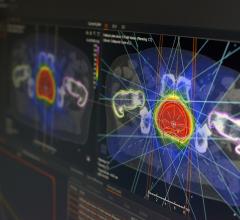

March 24, 2014 — Medical physicists met in Denver, Colo., March 15-18 for the American Association of Physicists in Medicine (AAPM) Spring Clinical Meeting, hosted at the Denver Marriott Tech Center. The meeting focused on helping medical physicists with the integration of emerging technologies into the clinical environment. Mirada Medical demonstrated its comprehensive suite of advanced deformable image registration (DIR) software tools to meeting attendees. The company utilizes its scientifically advanced DIR algorithms to provide practical tools to support treatment planning.

Mirada’s scientists have made their algorithms application and modality specific — carefully tuning internal parameters, such as deformable field smoothness, degree of freedom and similarity function sensitivity. This provides a strong basis for multi-modality contouring, auto contouring, dose deformation and composite dose, and it provides support for adaptive therapy and re-treatment decisions.